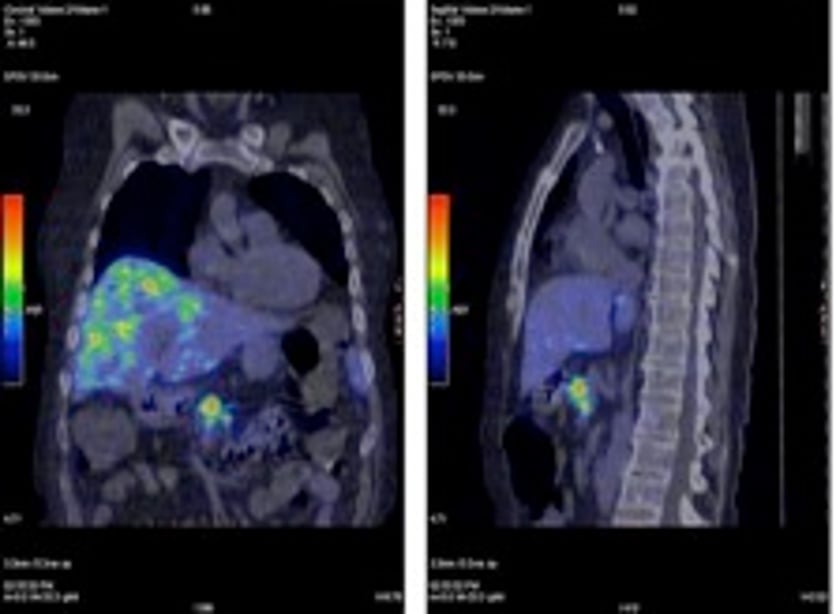

Positron emission tomography (PET)

During the last few years PET using 18F-labelled deoxy-glucose (FDG) has evolved as a powerful imaging modality in oncology. The recent introduction of PET-CT and also most recently PET-MRI, leads to several advantages over a standard PET. The anatomic localisation will be significantly improved. The positron-emitting radionuclides are generally produced in a low-energy cyclotron and the half-lives are usually short; 2-110 minutes. In practice the use of 11C and 18F-labelled PET tracers requires a cyclotron in the vicinity of the PET camera, but 18F can be transported within radius of about 2 hours. The PET tracers emit positrons which collides with an electron upon which both are annihilated and converted into high-energy photons. These travel in opposite directions and simultaneously reach the detector ring and the line of decay is registered. By collecting data from all detected decays during the acquisition, transaxial images may be reconstructed. The attenuation-corrected PET-images are regularly recalculated to provide images of standardized uptake values (SUVs).

Specific tracers for NETs are 18F-DOPA PET, 11C-5HTP-PET, 68Ga-DOTA-octreotate. 18F-L DOPA and 11C-L-DOPA has been used in a number of studies to visualize NETs with a sensitivity of somewhere between 50-70%. 18F-DOPA PET has also been informative in the visualization of medullary thyroid cancer. 11C-5-HTP-PET is more sensitive than 11C-L-DOPA and also 18F-DOPA-PET particularly in endocrine pancreatic tumors. In a comparative study between CT-scan, SRS and 5-HTP-PET the latter shows significant higher sensitivity and could also demonstrate more lesions than the other methods. The draw-back with this technique is that it is only available in very few centers, such as Uppsala and Gronningen. The technique can demonstrate tumors down to 3 mm. (Fig. 5, 6).

68Ga-DOTA-octreotate-PET (Fig. 7)

68Ga is a generator-produced positron emitter, which has come more and more in to clinical praxis and is also called "the poor mans PET". In several studies it demonstrated higher sensitivity than SRS and can be done in "one-stop" procedure. The better spatial resolution by PET speaks in favour of functional imaging by PET compared with SPECT and planar imaging with SRS.

68Ga-DOTA-octreotate-PET